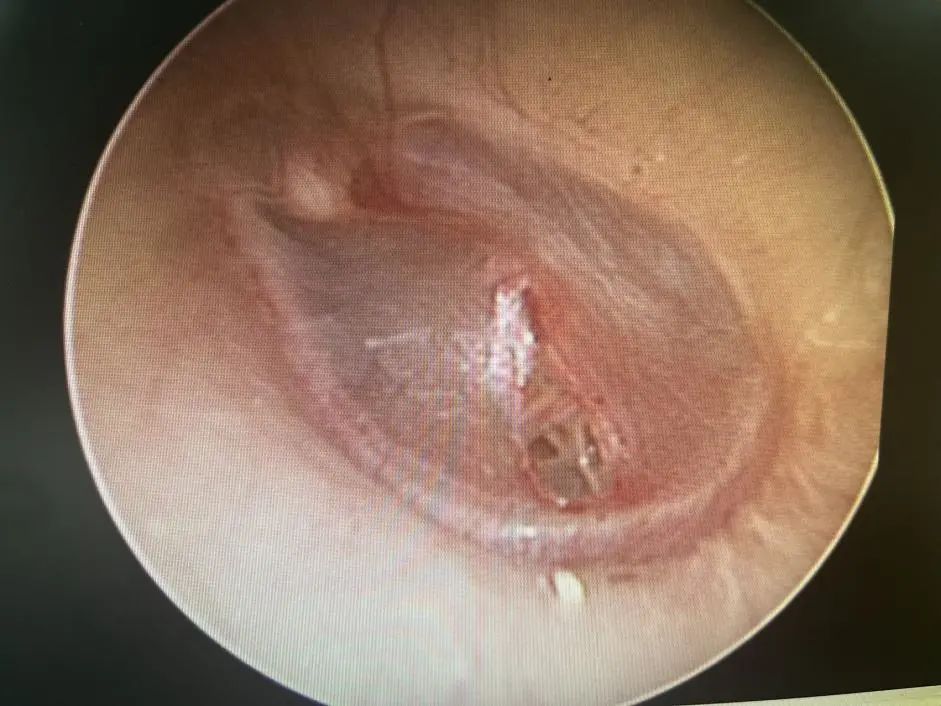

醫(yī)生在視頻耳內(nèi)鏡下發(fā)現(xiàn)左側(cè)鼓膜有一個(gè)破口,有血跡殘留在鼓膜上,還做了純音聽(tīng)閾檢測(cè),檢查結(jié)果顯示,小花的左耳聽(tīng)力呈中度傳導(dǎo)性耳聾。

鼓膜穿孔